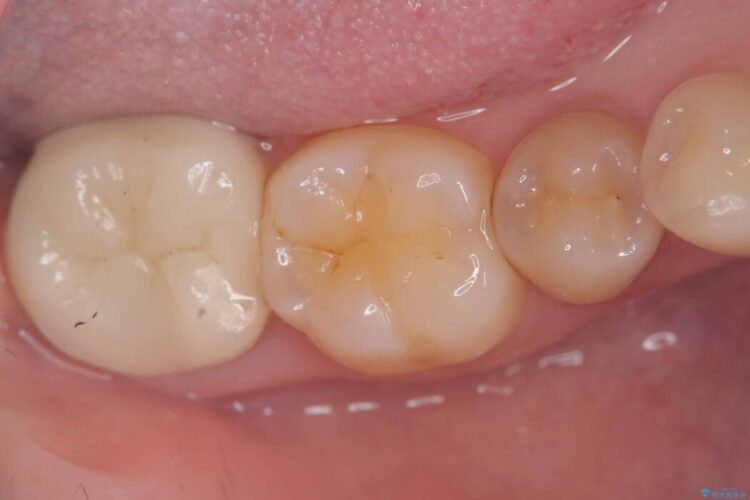

メタルフリー|全ての銀歯をセラミックへ

メタルフリー|全ての銀歯をセラミックへ ビフォー メタルフリー|全ての銀歯をセラミックへ アフター

口腔内の銀歯を全て無くし、白く健康的な状態にしたいとご来院された患者様です。